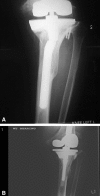

Background: The best method for managing large bone defects during revision knee arthroplasty is unknown. Metaphyseal fixation using porous tantalum cones has been proposed for severe bone loss. Whether this approach achieves osseointegration with low complication rates is unclear.

Methods: We retrospectively reviewed 27 patients who had 33 tantalum cones (nine femoral, 24 tibial) implanted during 27 revision knee arthroplasties. There were 14 women and 13 men with a mean age of 64.6 years. Preoperative diagnosis was reimplantation for infection in 13 knees, aseptic loosening in 10, and wear-osteolysis in four. Patients were evaluated clinically and radiographically using the score systems of the Knee Society and followed for a minimum of 2 years (mean, 3.3 years; range, 2-5.7 years).

Results: One knee with two cones was removed for infection. All but one cone showed osseointegration. One knee was revised for femoral cone and component loosening. There was one reoperation for femoral shaft fracture and one for superficial dehiscence. The mean Knee Society pain score improved from 40 points preoperatively to 79 points postoperatively. The mean function score improved from 19 points to 47 points.

Conclusions: Our observations suggest metaphyseal fixation with tantalum cones can be achieved. Longer-term followup is required to determine whether the fixation is durable.